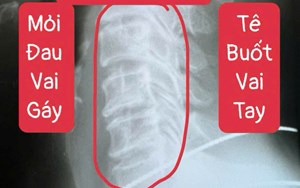

Địa chỉ : 50 Phan Huy Ích, Phường 15, Quận Tân Bình, TP. HCM.

CSKH: 0934 117 009

Tư vấn: 0903 933 011 (Ms.Điểu)/ 0934 117 009 (Mr. Nhung)

Hotline: 0903 933 011 - 028.3815.1615